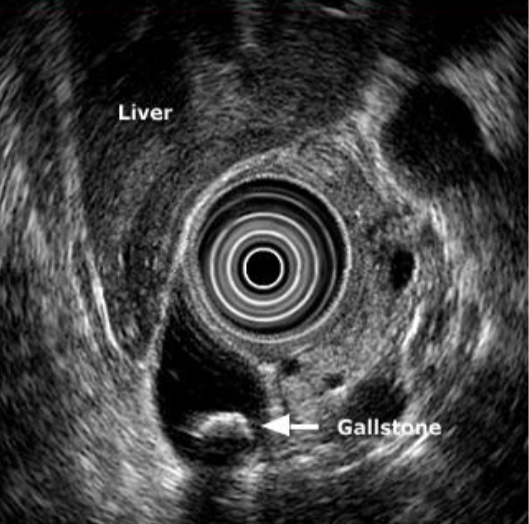

Endoscopic ultrasound

Transducer on tip of endoscope

More sensitive for sludge & small stones

Can exclude PUD

Endoscopic US

Endosonographic image of stone in common bile duct (with acoustic shadow)